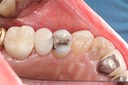

Alan Chinn #2 & 5 amalgam removal